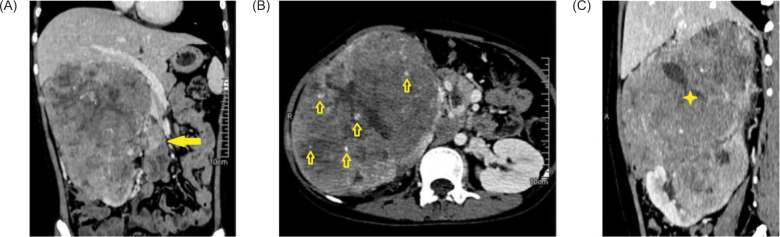

本报告叙述了一名女性儿童的诊断过程,她因腹部造影发现巨大肾肿块而出现血尿。对其进行了组织学评估和随后的免疫组化研究。TFE3和α-甲基酰-CoA-racemase的免疫组化表达强烈而明确,碳酸酐酶IX相应呈阴性,加上非常独特的临床、放射学、大体和显微镜检查结果,确诊为TFE3基因重排的肾细胞癌,这在菲律宾尚属首例。在资源匮乏的环境中,评估罕见疾病的分子模式基本不存在,本病例凸显了可靠、可负担和可获得的免疫组化研究的重要作用和重大诊断影响。认识到儿童和青少年肾脏恶性肿瘤的独特形态学、免疫组化和细胞遗传学特征,就能及时对这种侵袭性实体进行治疗干预。

This report recounts the diagnostic workup of a pediatric female who presented with hematuria secondary to a large renal mass visualized on abdominal imaging. Histologic assessment and subsequent immunohistochemistry studies were performed. Intense, unequivocal immunohistochemical expression of TFE3 and alpha-methylacyl-CoA-racemase with corresponding negativity for carbonic anhydrase IX, along with highly distinctive clinical, radiologic, gross, and microscopic findings confirmed the diagnosis of a renal cell carcinoma with TFE3 gene rearrangement - the first ever reported case in the Philippines. This case highlights the vital role and significant diagnostic impact of reliable, affordable and accessible immunohistochemistry studies in low-resource settings where molecular modalities for evaluating rare diseases are largely unavailable. Recognition of distinctive morphologic, immunohistochemical, and cytogenetic features in childhood and adolescent renal malignancies allows for the timely institution of therapeutic interventions for this aggressive entity.